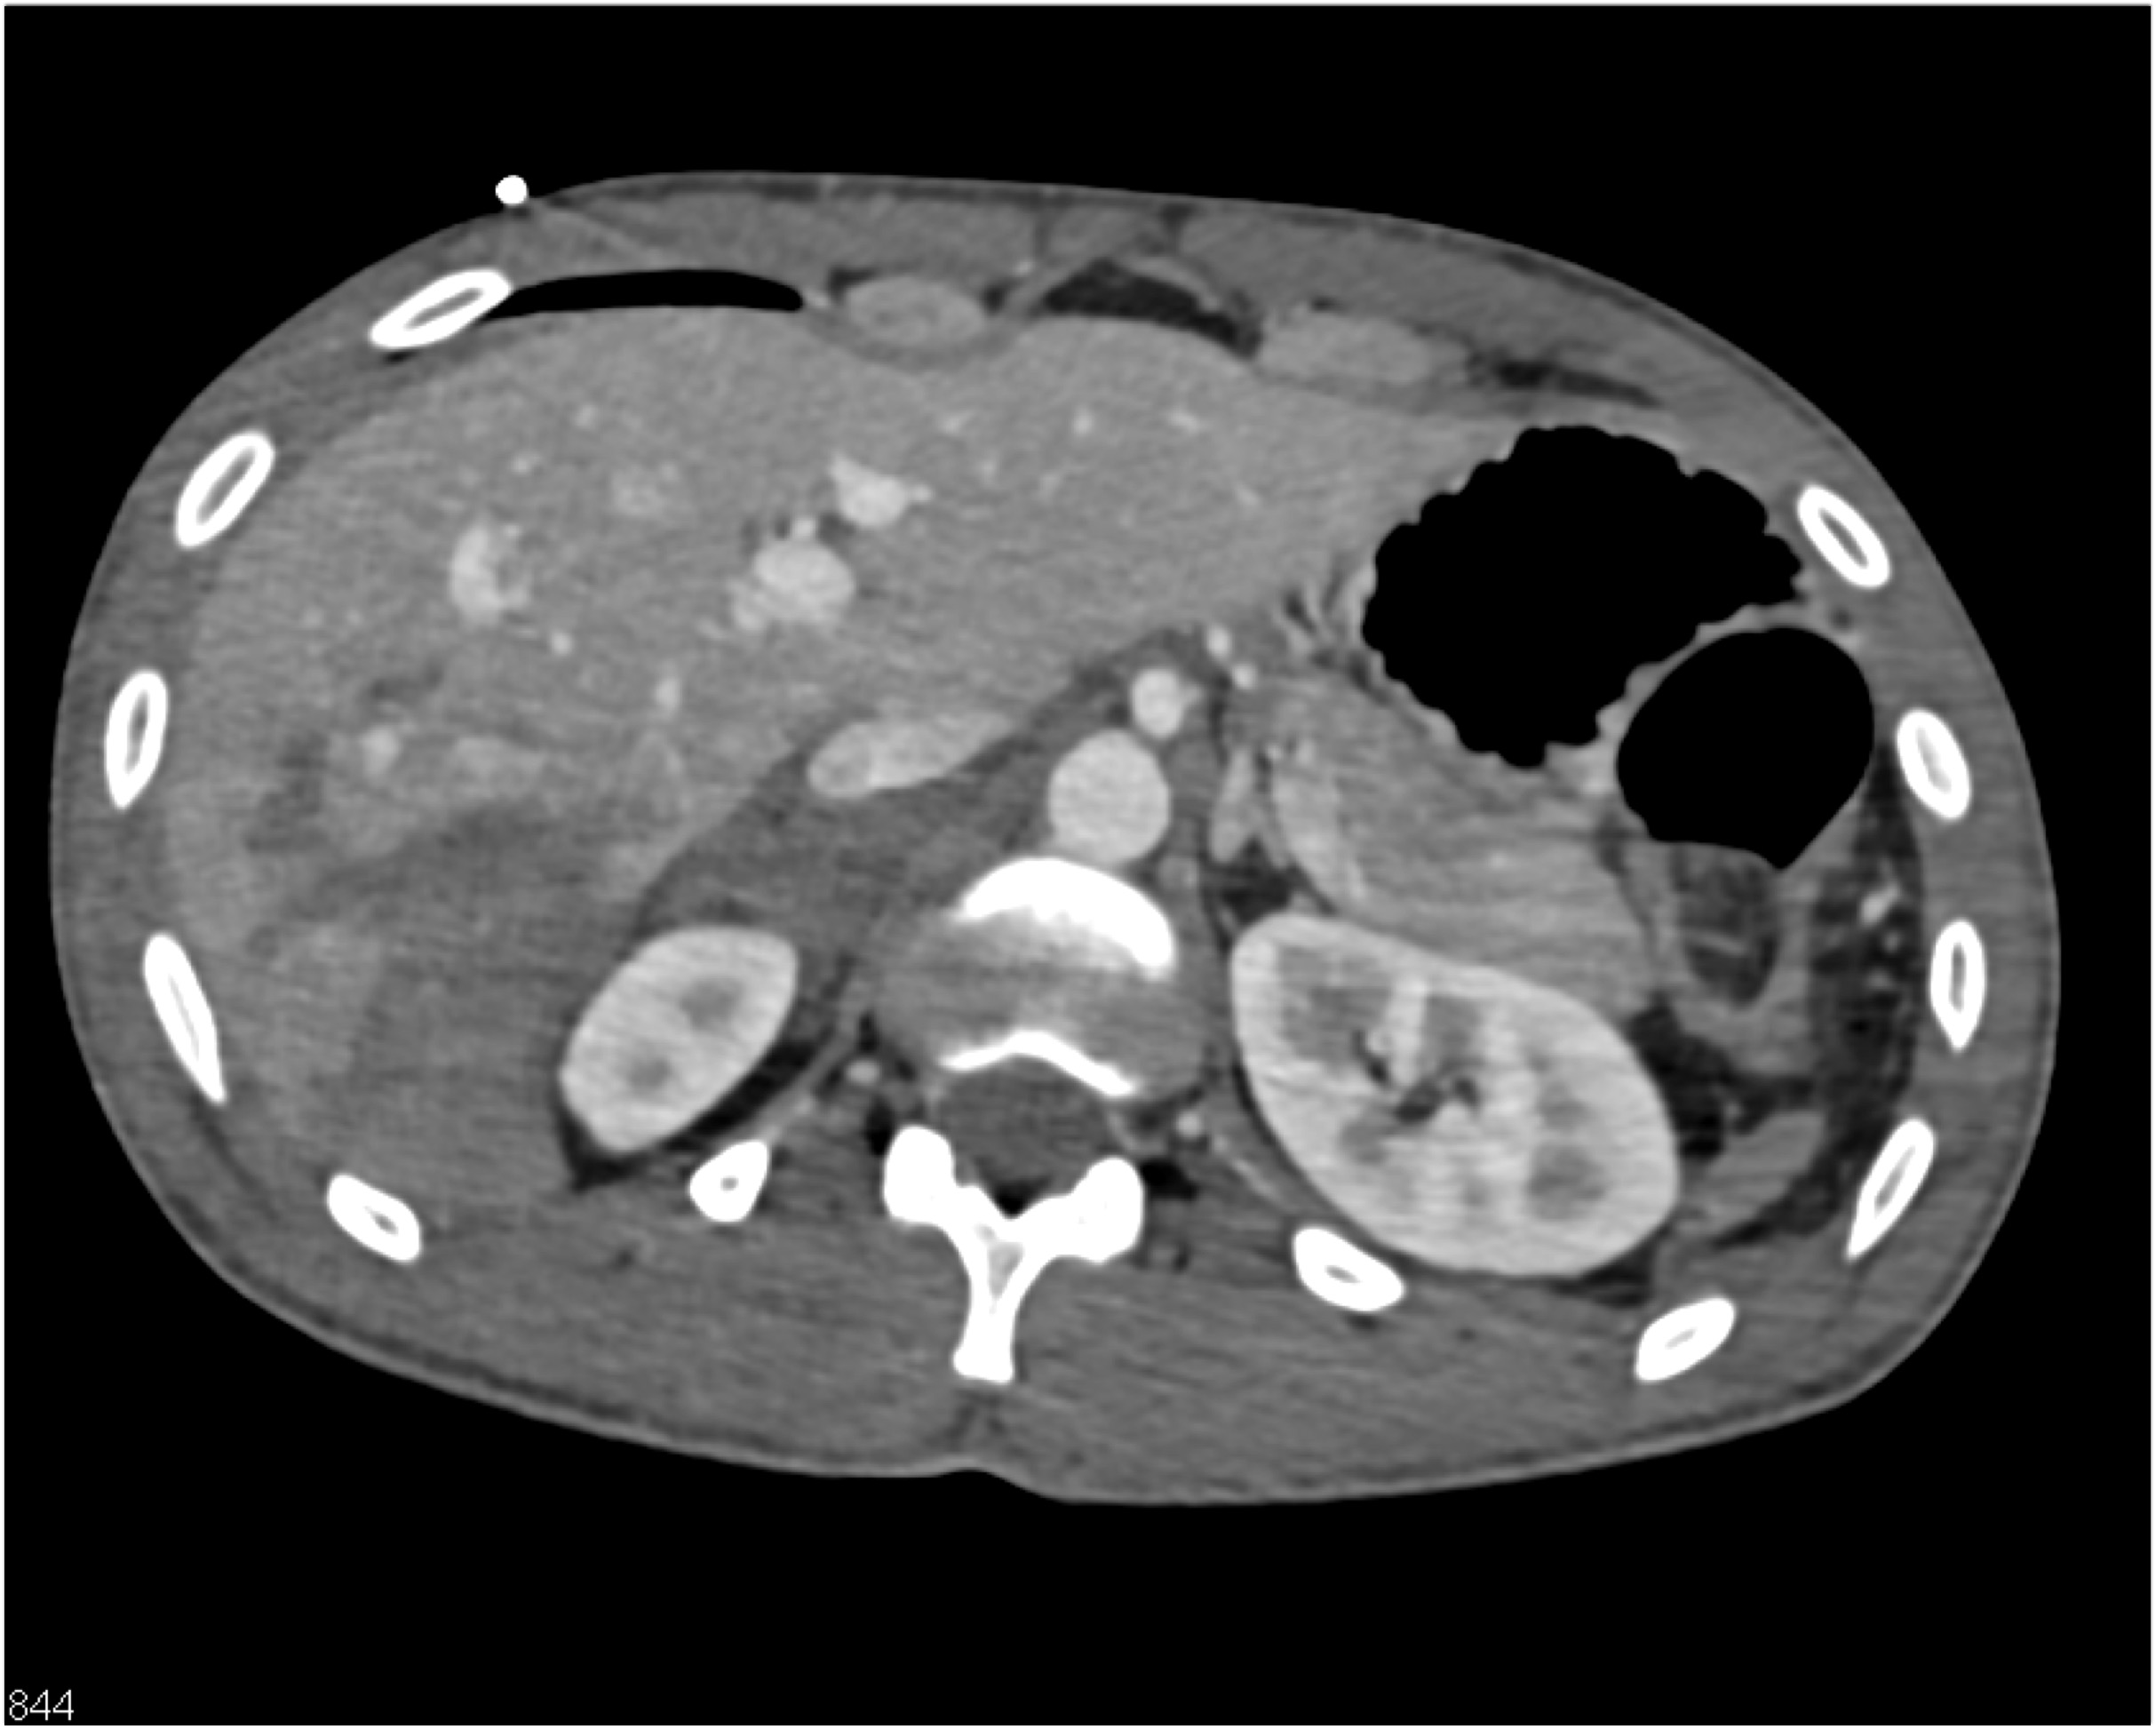

2) In this patient with a palpable right abdominal wall mass the best dx is?

rectus sheath hematoma

lymphoma

desmoid tumor

metastatic renal cell carcinoma